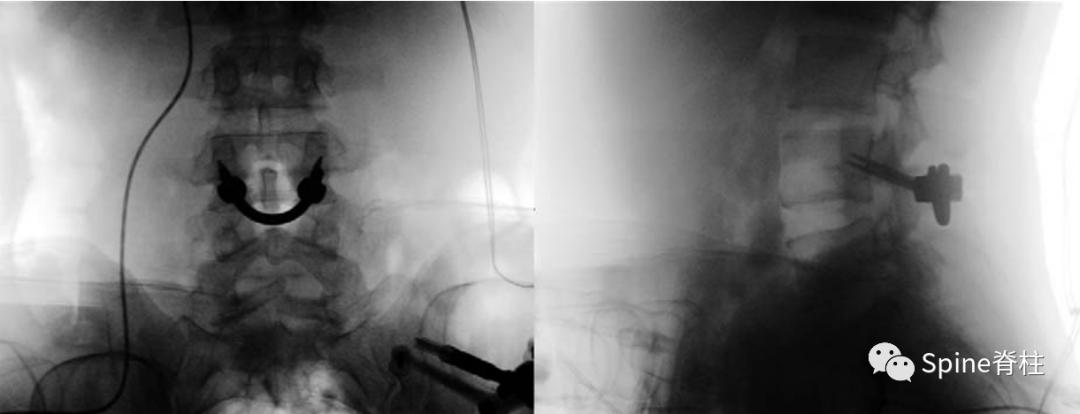

随着内固定的发展,既往峡部单纯修复植骨因融合率低、卧床时间长,现已很少应用。而植骨修复并节段固定有多种方法,包括Scott接线法、Buck螺钉法、Louis的蝶形板、钉钩技术(椎弓根螺钉和钩-棒系统)、U形棒等。从临床角度看,钉钩技术可以用刚性植入物固定断裂的峡部,并沿椎板方向施加作用力,有效稳定峡部,这对于达到更好的骨性愈合是至关重要的。理论上,此种方法更符合生物力学,对邻近节段影响小,但应把握好适应症,建议单纯腰椎峡部裂伴或不伴轻度滑脱患者可行植骨修复并节段固定。

1. 椎弓根螺钉-钉钩系统

PMID: 9199377

PMID: 15699811

PMID: 17520298